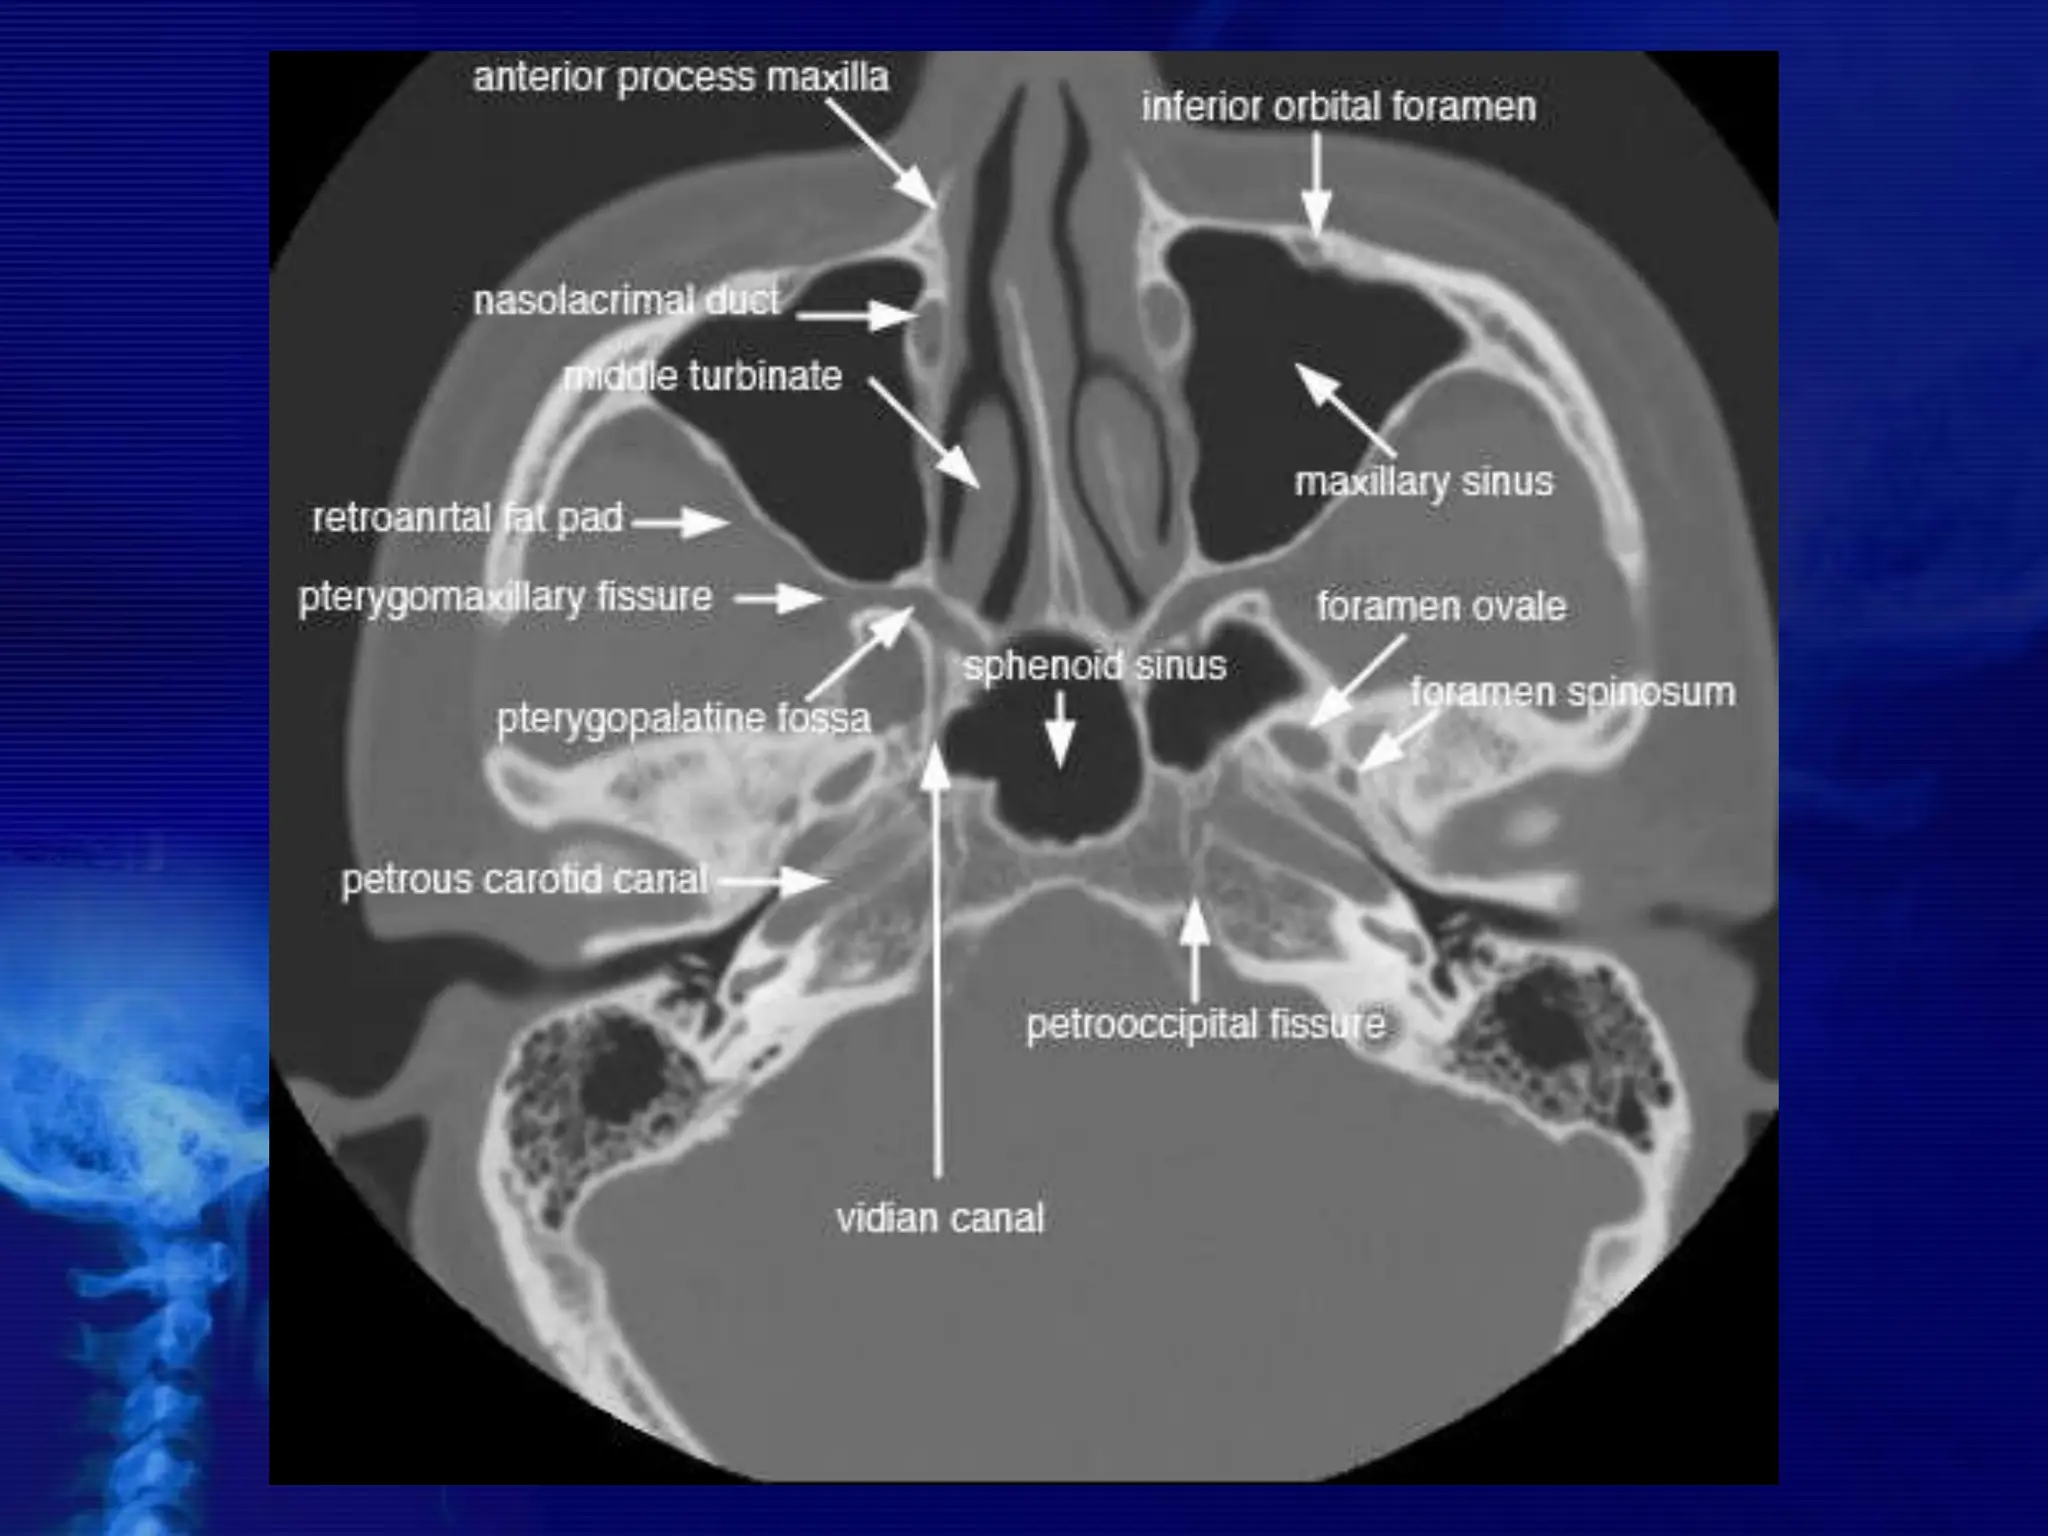

CROSS SECTIONAL ANATOMY –

AXIALS